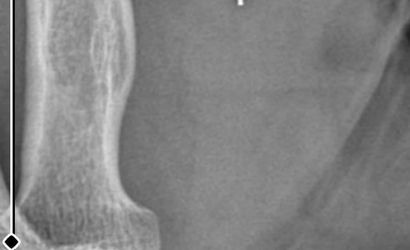

Ameliyatların ardından kolunda ağrılar hissettiğini söyleyen Güleryüz, kolunda metal parça bulunduğunu ve bu parçanın parmak bölgesinden dirseğe doğru ilerlediği iddiasını dile getirdi. Ayrıca çalıştığı fabrikada temizlik personeli olan Güleryüz'ün tedavi sürecinde işten çıkarıldığı öğrenildi.